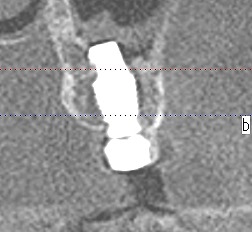

左上の4,5,7番部の難症例 インプラント埋入 ソケットリフトテクニックにてインプラント埋入|お知らせ |広島市安佐南区の歯科医院 左上の4,5,7番部の難症例 インプラント埋入 ソケットリフトテクニックにてインプラント埋入 トップ お知らせ・ブログ お知らせ 左上の4,5,7番部の難症例 インプラント埋入 ソケットリフトテクニックにてインプラント埋入 左上の4,5,7番部の難症例 インプラント埋入 ソケットリフトテクニックにてインプラント埋入 術前のパノラマになります 術中のパノラマになります 術後のパノラマになります 口腔内になります 術中のガイドピンになります インプラント埋入時になります 縫合して終了となります ソケットリフトにて持ち上げています 綺麗に入りました Web診療予約 初めての方へ 選ばれ続ける理由 院内設備について 歯が痛いしみる一般歯科 歯がぐらぐらする歯周病 健康な歯を保ちたい予防歯科 子供の虫歯予防をしたい小児歯科 銀歯をセラミックに審美歯科 白い歯を目指しませんか?ホワイトニング 矯正専門医がいるので安心矯正歯科 抜けた歯を補いたいインプラント・入れ歯 医院案内 スタッフ紹介 メリィハウス歯科クリニックオフィシャルホームページ ラベンダー歯科クリニックオフィシャルホームページ お知らせ・ブログ ホーム 診療科目 一般歯科 歯周病治療 予防治療 小児歯科 審美治療 ホワイトニング 矯正歯科 入れ歯・インプラント マウスピース矯正 初めての方へ 院長・スタッフ 設備紹介 医院案内・アクセス メニューを閉じる